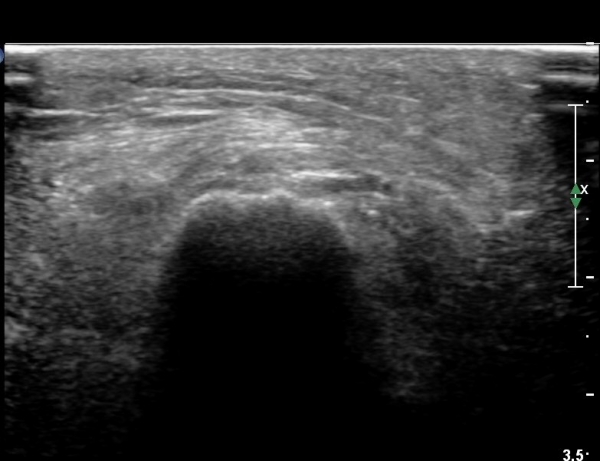

¹«¸­ ¿À±Ý ºÎÀ§ Ⱦ´Ü¸é°Ë»ç¿¡¼­ °æ°ñµ¿¸Æ Ç¥Ãþ¿¡ ºñ°ñ½Å°æ°ú °æ°ñ½Å°æÀÌ ºÐ¸®µÇ¾î °üÂûµÈ´Ù(»çÁø 1).